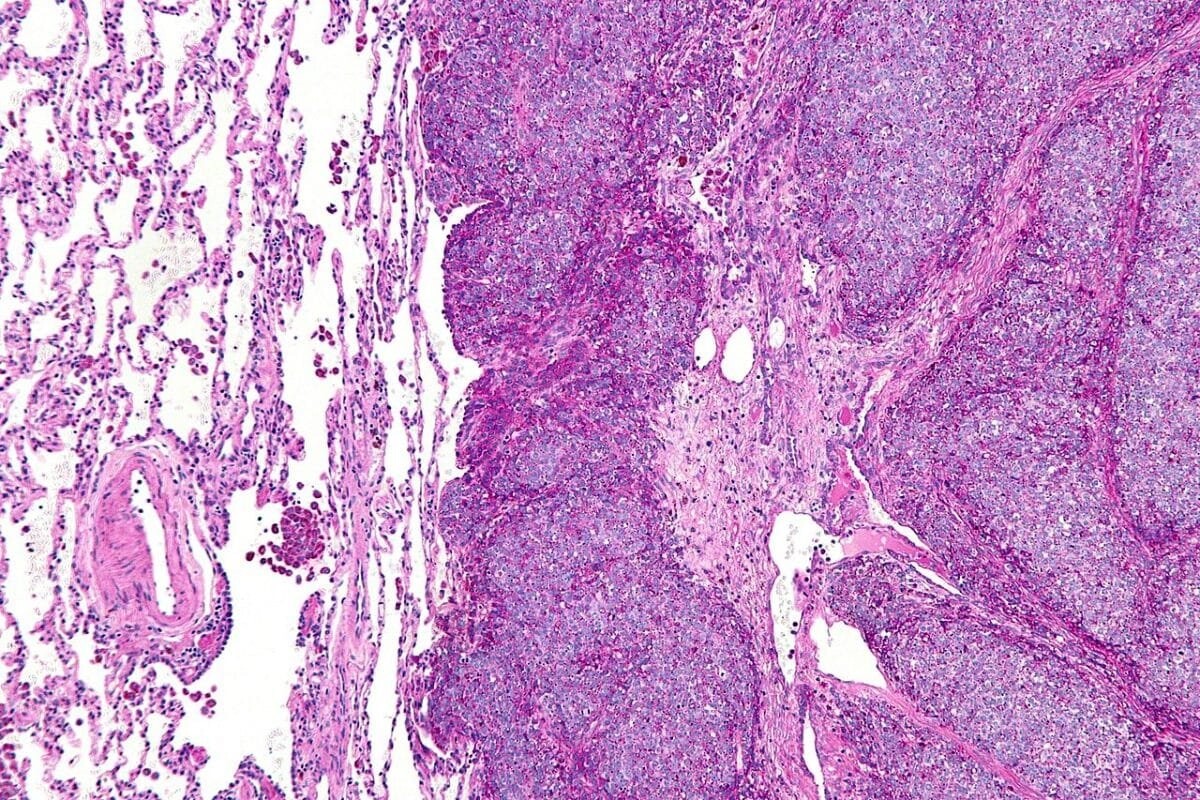

На фото: Микрография метастатической саркомы Юинга (справа на изображении) в нормальном легком (слева на изображении) / © Nephron, Wikipedia